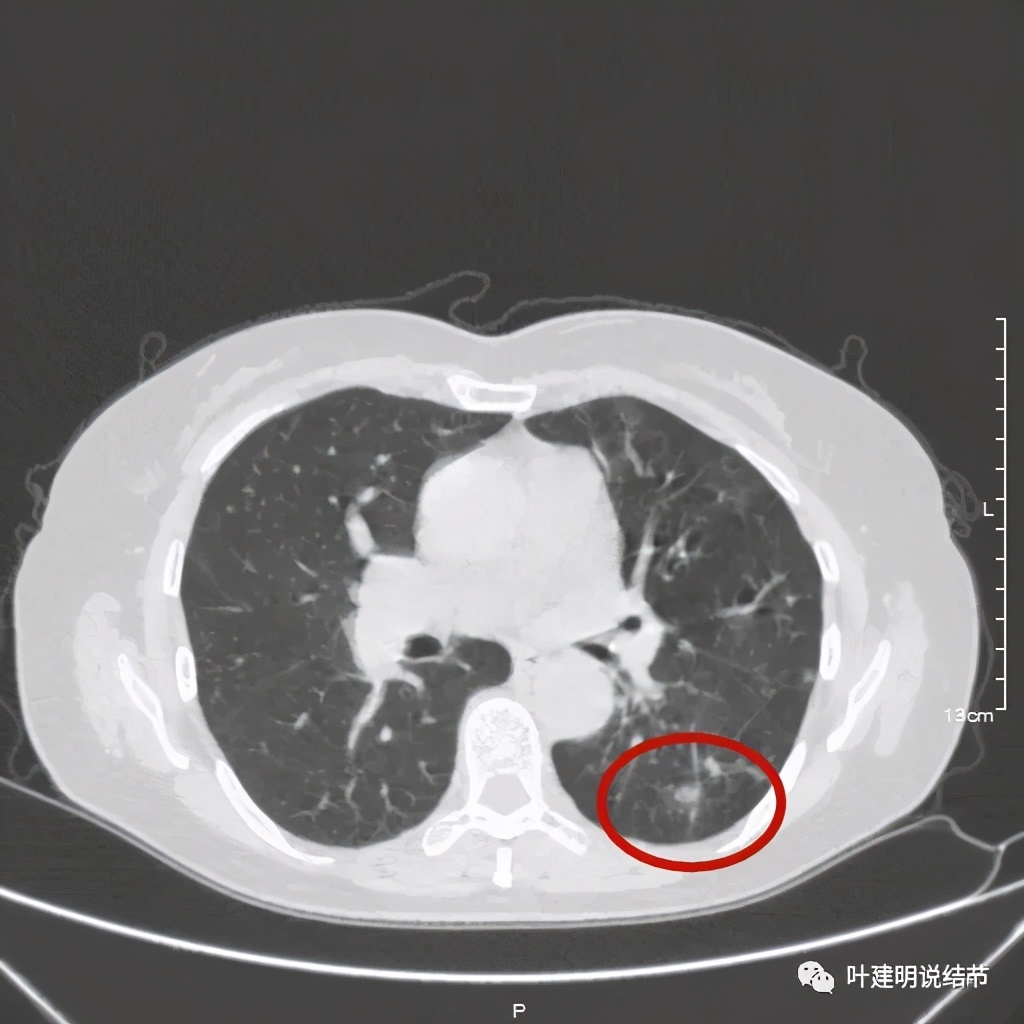

可见同样部位的左下结节已经较去年密度明显低了一些,说明有所吸收了!基本上已经只是磨玻璃密度了。那么其他病灶的情况呢?

也是有所变化,但病灶仍仍在,是异常的。最后这同图上还见到似乎也是实性伴小空腔的病灶(红色三角形标注处),是不是与之前的病灶有点像?